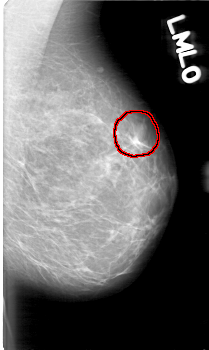

D_4080_1.LEFT_MLO

LEFT_MLO LINES 5236 PIXELS_PER_LINE 3121 BITS_PER_PIXEL 12 RESOLUTION 43.5 OVERLAY

FILE: D_4080_1.LEFT_MLO.OVERLAY

TOTAL_ABNORMALITIES 1

ABNORMALITY 1

LESION_TYPE MASS SHAPE OVAL MARGINS OBSCURED

ASSESSMENT 0

SUBTLETY 5

PATHOLOGY BENIGN

TOTAL_OUTLINES 1

BOUNDARY